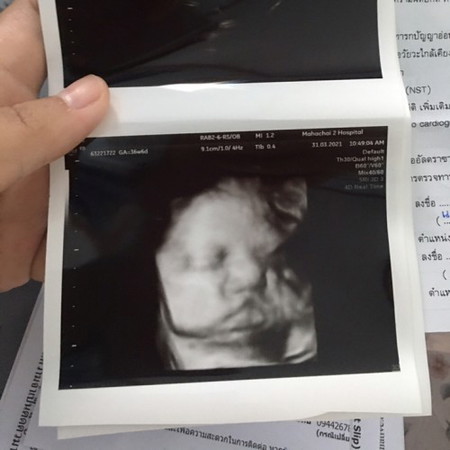

13 เมษา หมอนัดผ่าคลอด ตื่นเต้นจัง

แม่ๆท่านไหนเคยผ่าคลอดเจ็บไหมคะ กลัวไปหมดเลย ❤️👶🏻